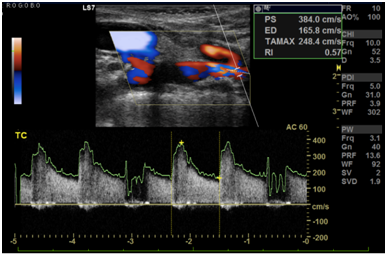

Cranioencephalic computerized tomography excluded acute ischemic lesions.CDS revealed severe stenosis of the innominate artery (PS 38 cm/s) (Figure 1), occlusion of right vertebral artery, total flow inversion of the right internal carotid artery (ICA) (Figure 2), partial endosystolic flow inversion of right CCA (Figure 3) and low amplitude anterograde flow of right external carotid artery, no significant lesions were found on the left carotid axis. Computerized tomography angiography (CTA) excluded significant carotid lesions and revealed pre-occlusive stenosis of the innominate artery by a calcic lesion (Figure 4).Surgical approach consisted of ultrasound-guided puncture of right brachial artery and surgical exposure of right CCA. Brain protection was achieved by direct clamping of the common carotid artery and subsequently carotid and axillary retrograde endovascular access was obtained. Placement of 6F introducer on brachial artery and 8F on right CCA (Figure 5). After pre-dilatation with a 4x40mm balloon (Admiral Xtreme™, Medtronic), a kissing stent technique was performed with a 6x59mm covered stent (AdvantaV12™, Getinge) on the right CCA and 7x57mm balloon-expandable stent (Visi-Pro™, Medtronic) on the right subclavian artery. At the end of the procedure direct expulsion of eventual embolic material was performed prior to declamping and a good permeability of the revascularized arteries was verified (Figure 6). Clamping time was under 1minute. The postoperative period was uneventful and patient was discharged 3days later.

Figure 2 Right internal carotid artery with total flow inversion.